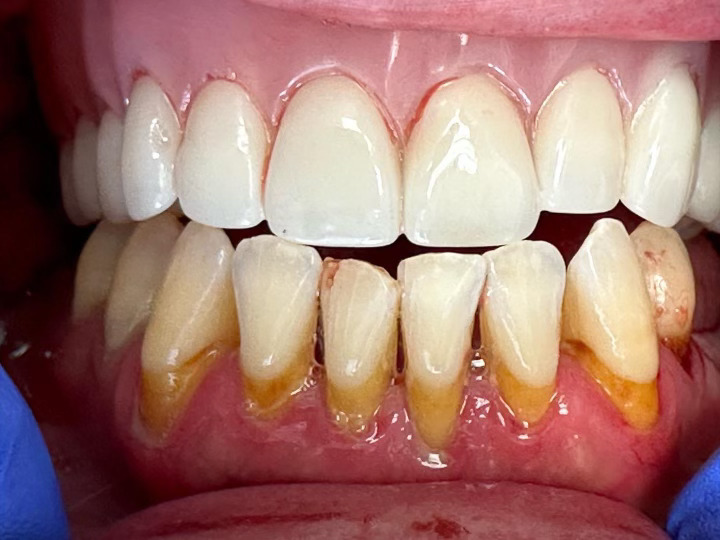

Case Study: Dental Implant

A patient with a missing tooth received a dental implant, restoring both function and aesthetics.